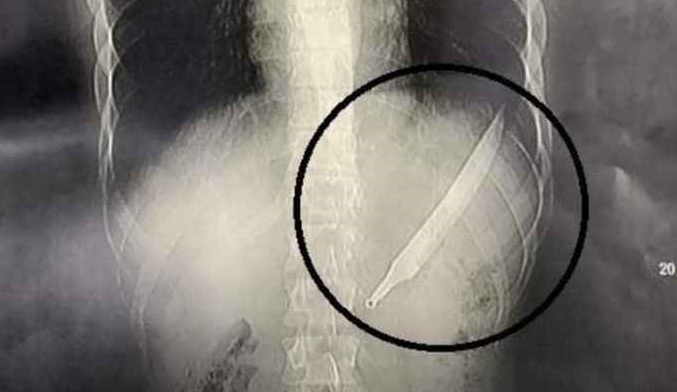

يبتلع سكيناً طوله 27 سم .. والأطباء يصنعون معجزة

وكالة الناس – ابتلع شاب مصري سكينا طوله 27 سنتيمترا إلا أن الأطباء نجحوا في إخراجه وإنقاذ حياة المريض، في واقعة أثارت الدهشة.

وقال وكيل وزارة الصحة في محافظة الدقهلية سعد مكي، إن “فريقا طبيا تمكن من استخراج سكين كبير من بطن مريض”، بعد جراحة معقدة.

وأضاف مكي: “حضر المريض إلى المستشفى الدولي في المنصورة يعاني آلاما شديدة في البطن، وبعمل الأشعات والفحوص تبين وجود جسم غريب”.

وتابع: “تمكن الفريق الطبي من إجراء عملية جراحية لاستخراج الجسم الغريب (سكين)، وتكللت العملية بالنجاح وخرج المريض بحالة مستقرة”.

كما أكد مدير المستشفى أحمد حشيش أن السكين له مقبض بلاستيكي ونصل حديدي حاد، كان من الممكن أن يحدث ثقبا في معدة المريض.

وتوقع حشيش أنه “من الممكن أن يكون المريض أدخله خطأ بالاتجاه المعاكس إلى فمه، أي من المقبض وليس من النصل، خاصة أنه لا يعاني أي مشاكل نفسية وبكامل قواه العقلية”.